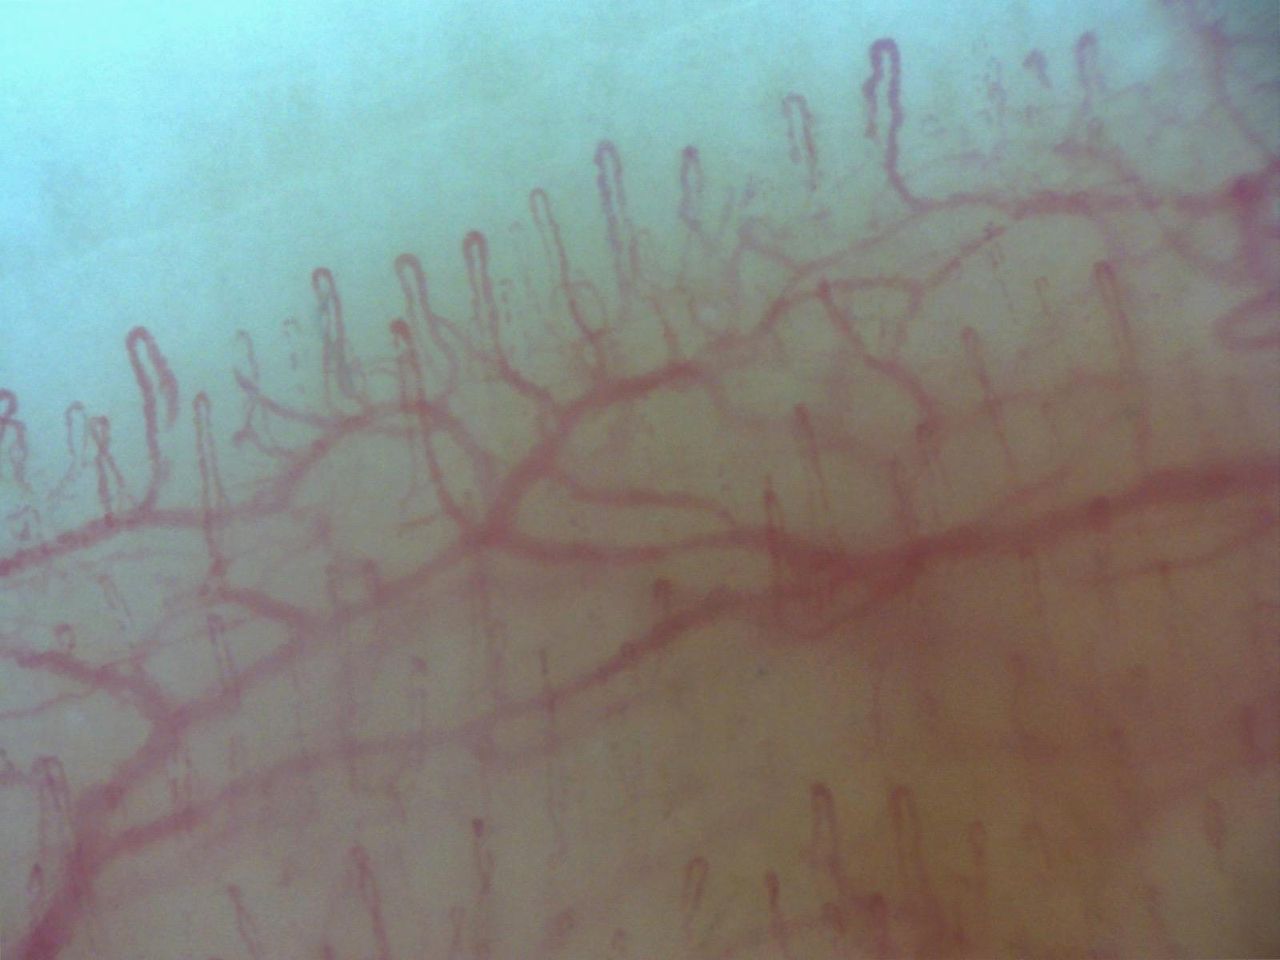

Nel mio percorso formativo ho conseguito esperienza nell'ecograifa articolare, nelle infiltrazioni articolari, nelle biopsie sinoviali e nella gestione delle terapie immunosoppressive con farmaci biotecnologici

• Capillaroscopia con videoregistrazione

60 € - 88 €

• Cerba Healthcare Lazio S.r.l - Fonte Meravigliosa capillaroscopia con videoregistrazione  •